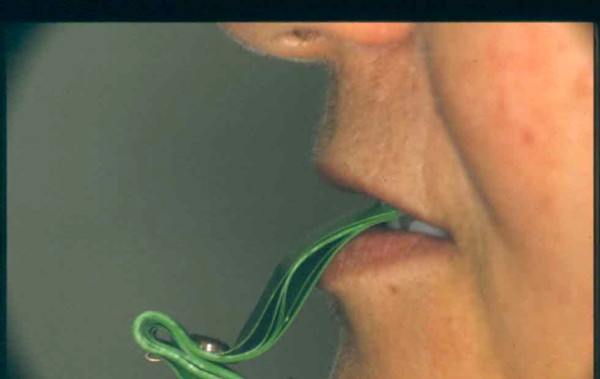

APRECIACIONES DIAGNÓSTICAS EN BASE A LA APERTURA MENTAL DEL CLÍNICO FRENTE A LO QUE EL PACIENTE PROPONE EN MUCHAS OCASIONES , LA DEMANDA DE LOS PACIENTES NOS INCLINAN A FOCALIZAR NUESTRA ATENCIÓN EN LAS PIEZAS DE LAS CUALES EL ENFERMO SE QUEJA. PACIENTE SEXO FEMENINO, 55 AÑOS, SE PRESENTA A LA CONSULTA DERIVADA POR COMPAÑERO GENERALISTA, QUIEN LLEVA MESES PROCEDIENDO A LA «DESINFECCIÓN» DE UN PRIMER PREMOLAR IZQUIERDO, EL QUE SE PRESENTA ABIERTO EN SU CONDUCTO EN EL AFÁN DE PERMITIR EL ESCAPE DE GASES DE UNA GANGRENA PULPAR. A LA INSPECCIÓN CLÍNICA SE OBSERVAN FACETAS PARAFUNCIONALES DE TERCER GRADO , ASINTOMÁTICAS, CON EVIDENTES DIFICULTADES MASTICATORIAS Y ESTÉTICAS , FALTA TOTAL DE SUS MOLARES INFERIORES, Y ADELANTAMIENTO PRONUNCIADO DE SU MANDIBULA, LA QUE CUESTA MANIPULAR DEBIDO A LA SITUACIÓN DE ESPASMO DE CASI TODA SU MUSCULATURA GNATICA. SE ESTUDIA EL CASO RADIOLOGICAMENTE, Y SE RELAJA EL SISTEMA MEDIANTE LAM. DE LONG REALIZANDO UN MONTAJE EN LA ORC OBTENIDA. NO SATISFECHOS CON EL RESULTADO, CONFECCIONAMOS UN JIG DE LUCIA, EL QUE DEJAMOS EN BOCA TODA UNA NOCHE, AL CABO DE LA CUAL REALIZAMOS UN NUEVO REGISTRO REALIZAMOS UN ENCERADO RÁPIDO DEL CASO, Y CONFECCIONAMOS UNA ESTRUCTURA OCLUSAL PLASTICA, QUE ADEMÁS REPONGA EL ASPECTO ESTÉTICO PERDIDO (FÉRULA DE RELAJACIÓN DE COMPONENTE ESTÉTICO), LO QUE PERMITE AL ENFERMO LUEGO DE DOS DÍAS DE USO, NO SOLO CORROBORAR LA COMODIDAD MASTICATORIA Y LA FALTA DE SÍNTOMAS MUSCULARES, SINO TAMBIÉN OBSERVAR APROXIMADAMENTE LA DIFERENCIA ENTRE LA SITUACIÓN INICIAL Y LO QUE PUEDE LOGRARSE MEDIANTE EL TRATAMIENTO. EL PACIENTE ADVIERTE LA MEJORÍA DE LA SITUACIÓN. ACEPTADO POR PARTE DEL MISMO EL TRATAMIENTO SUGERIDO, CREAMOS UN JUEGO COMPLETO DE PROVISORIOS EN BASE AL ENCERADO, Y PROCEDEMOS A TRATAR LA INFRAESTRUCTURA, QUE CONSISTE EN LAS ENDODONCIAS, SUS REFUERZOS A PERNOS DE ORO, LOS ASPECTOS PERIODONTALES DEL CASO, Y DOS IMPLANTES INFERIORES CON TÉCNICA SEMISUMERGIDA ,DE 5 MM DE ANCHO POR 12 DE LONGITUD, CON ANILLO DE ZIRCONIO , A LA ESPERA DE OSTEOINTEGRACIÓN, TRANSCURREN TRES MESES EN EL USO DE UNA NUEVA OCLUSIÓN CONSTITUIDA POR LOS PROVISIONALES, SEGÚN EL ENCERADO, QUE SE REALIZÓ SIGUIENDO LOS CÁNONES DE UNA OCLUSIÓN ORGÁNICA. COMPROBADA LA EFICACIA DE LA NUEVA SITUACIÓN, CON SUS DISCLUSIONES LATERALES Y POSTERO ANTERIORES CORRECTAS, CARECIENDO YA DE SINTOMATOLOGÍA MUSCULAR (SIN MIALGIAS, SIN MIOSITIS, Y CON UN GRADO DE APERTURA DE 4,50 CM), Y SIN SIGNOS EVIDENTES DE DESGASTE SOBRE EL MATERIAL DE LOS PROVISORIOS, ES DECIR: VERIFICANDO QUE EL PACIENTE YA NO BRUXA, VERTICALIZANDO EL CICLO MASTICATORIO /OTORGANDO ORC/ DIMENSIÓN VERTICAL /PROTEGIENDO A LAS PIEZAS `POSTERIORES DE IMPACTOS LATERALES RECIEN ENTONCES , MONTAMOS EN ARTICULADOR SEMI AJUSTABLE LOS MODELOS DE TRABAJO DEFINITIVOS. CONFECCIONAMOS ENTONCES LAS COFIAS INFRA PORCELANA, EN PORCELANA DE ALTA DENSIDAD EN EL SECTOR ANTERIOR Y EN ORO GALVÁNICO PARA EL SECTOR POSTERIOR PARA LUEGO COMPLETAR LA GUIA ANTERIOR , VERIFICANDO LA ALTURA DE LOS INFERIORES RESPECTO DEL LABIO INFERIOR Y CORROBORANDO LOS PUNTOS DE CONTACTOS INTER CANINOS, QUE CENTRALIZAN LA MANDIBULA Y VERTICALIZAN EL CICLO MASTICATORIO Y LAS DISCLUSIONES CANINAS QUE OTORGARÁN PROTECCIÓN A LOS SECTORES POSTERIORES. POSTERIORMENTE CHEQUEAMOS LA DISCLUSIÓN EN PROPULSIVA DE LA GUIA ANTERIOR YA TERMINADA. FIG38 FIG39 UNA VEZ OBTENIDO UN COMANDO ANTERIOR EFECTIVO, COMO LO ES LA GUIA ANTERIOR CON TODOS SUS COMPONENTES, PROCEDEMOS A REALIZAR LAS TABLAS PREMOLAR / MOLAR DE AMBOS LADOS Y OBSERVAMOS QUE LOS PUNTOS INTEROCLUSALES DE CONTACTO SEAN SUFICIENTES Y CUMPLAN SU OBJETIVO DE OTORGAR ESTABILIDAD MESIO DISTAL Y VESTÍBULO LINGUAL. TRANSCURRIDO UN AÑO DE FINALIZADO EL TRATAMIENTO, REALIZAMOS UN CHEQUEO POST OPERATORIO DEL CASO, EN TODOS LOS PARÁMETROS ANTERIORMENTE MENCIONADOS, Y OBSERVAMOS LA ABSOLUTA ESTABILIDAD DEL MISMO EN TODOS SUS NIVELES Y TEJIDOS.